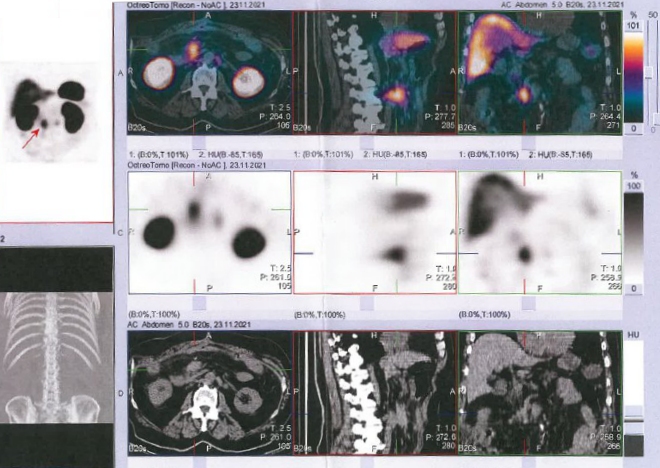

/ Obr. č. 2: Fúze SPECT/CT břicha a pánve 24 hod. po aplikaci OctreoScanu.

Popis: Prokazujeme dva okrsky patologicky zvýšené hustoty somatostatinových receptorů v paketu LU na mesenteriu vpravo ve výši L2 a v LU v retroperitoneu paraortálně vlevo ve stejné úrovni - svědčí nejspíše pro metastázy NET.